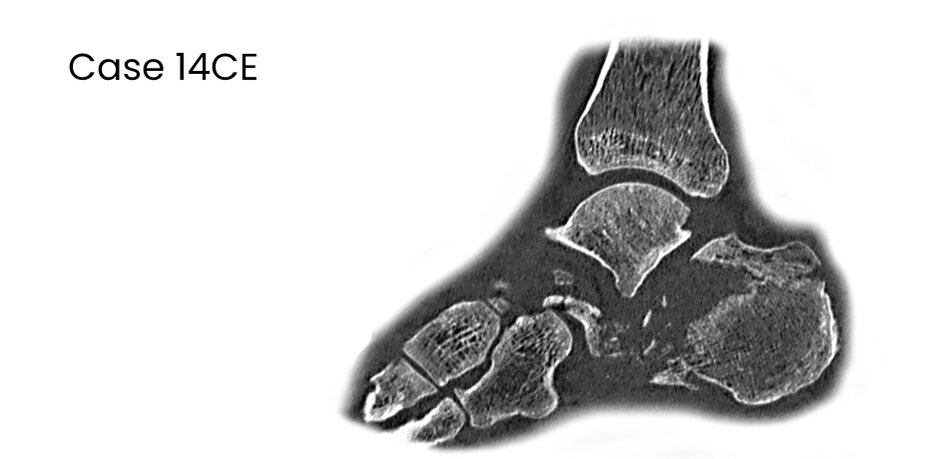

14CE, male 52 y, comminuted, MIT,surgery 2 days after trauma, secundary arthrodesis